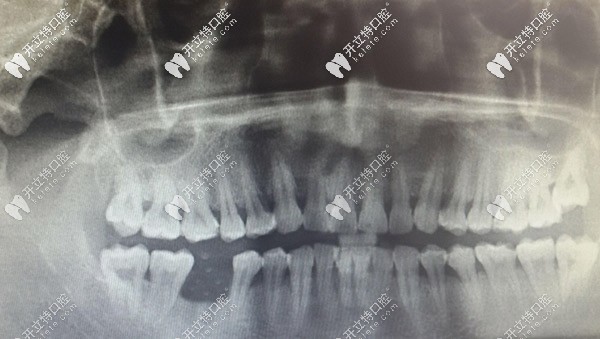

從顧客的曲斷X線片,可以看到右下6的牙槽骨明顯低于相鄰牙齒,已經(jīng)吸收,出現(xiàn)三度松動(dòng)。右下6也出現(xiàn)了二度松動(dòng),勉強(qiáng)保留一定的要和功能。

半個(gè)月后來復(fù)診,查看牙窩有膿液溢出,且腫脹沒有消退,決定拍片看。片子顯示右下5有陰影,且陰影有一高密度區(qū),診斷有死骨形成,局麻取出死骨。

之后有來復(fù)診,右下5區(qū)還是腫脹有膿溢出。拍了曲斷牙片后顯示無異常,針對(duì)此情況,拍CBCT片顯示右下4根尖有少許陰影,其他都是陰性。